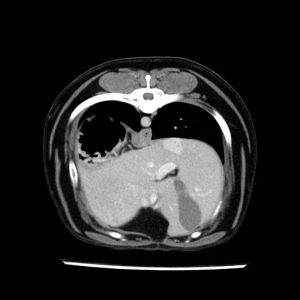

La lesione focale epatica , la ceus,la Tac e il chirurgo .